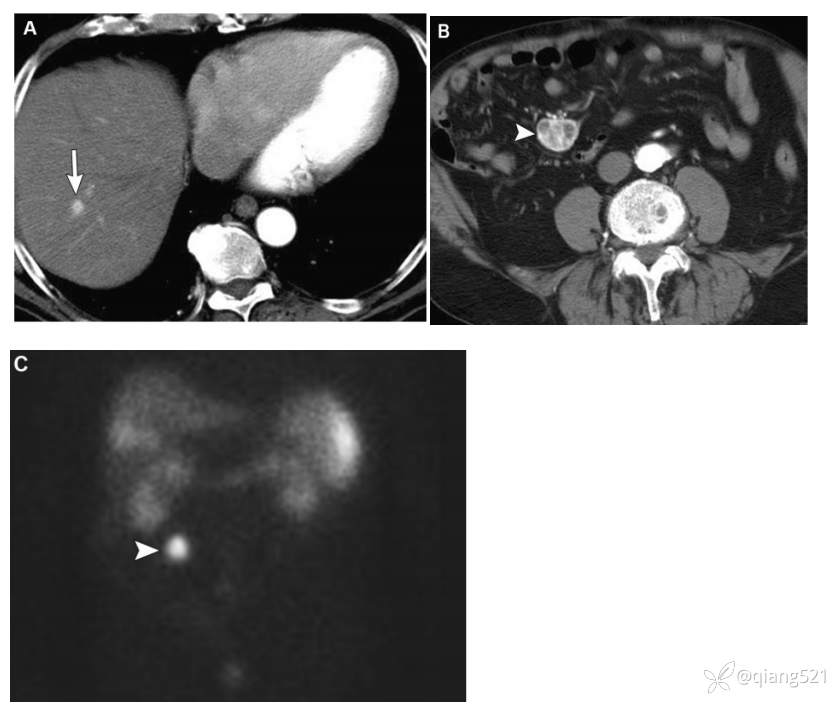

一名89岁的男性,患有转移性类癌。

横断上腹部(A)和中腹(B)的CECT显示右下象限不均匀强化的肿块(B中的箭头),右肝有一个微小的富血管病变,可能是转移性病变(A中的箭头)。患者血清5-HIAA水平升高。~(111)C-奥曲肽核素扫描显示肠系膜肿块有浓集的放射性示踪剂